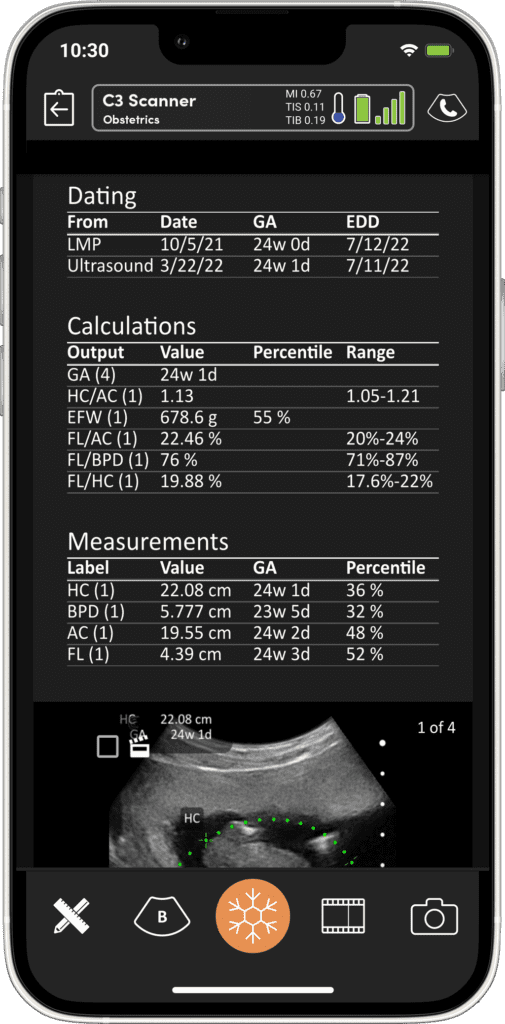

Imagerie Obstétricale Optimisée

I feel more confident with my ultrasound exams since I’ve started using OB AI. I love how the AI makes the app light up when things are perfectly lined up – I can see this really helping both seasoned clinicians and those who are starting their ultrasound journey.